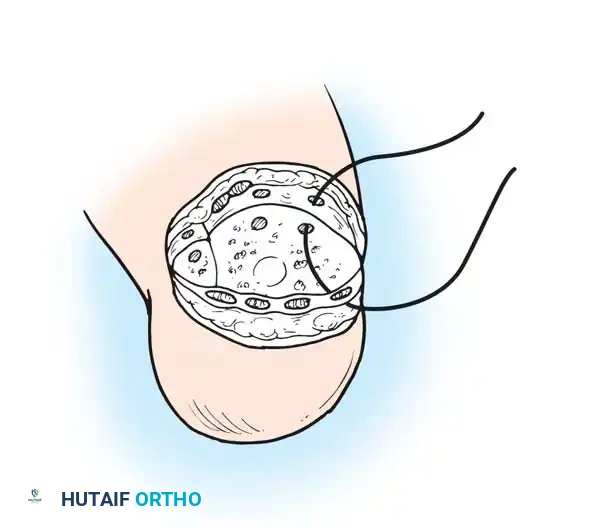

Step 6: Anchoring the Heel Pad (Wagner Technique)

To prevent the disastrous complication of posterior heel pad migration, the pad must be rigidly fixed to the distal tibia.

* Drill several small holes through the anterior edge of the distal tibia and fibula.

- Pass heavy, nonabsorbable sutures through these drill holes and anchor them securely to the robust deep fascia lining the heel flap.

Step 7: Closure

- Approximate the skin edge of the heel flap to the anterior flap using interrupted nonabsorbable sutures. Ensure there is absolutely zero tension on the closure.

- Crucial Step: Large, protruding tags of skin ("dog ears") will form at the medial and lateral ends of the suture line. Never excise these. They carry the primary blood supply to the heel flap and will naturally remodel and shrink under postoperative bandaging.